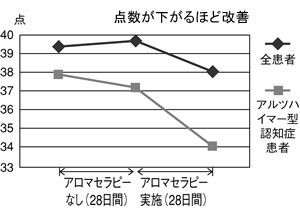

| 図2 アロマセラピーの知的機能への効果(GBS-A検査) |

|

最後に、実践してみて興味深い結果が出たものを紹介します。1つはアロマセラピーです。アロマオイルを使って香りを嗅ぐ方法です。介護老人保健施設でアロマセラピーを試したところ、改善しました(図2)。

実はアルツハイマー型認知症は、最初に匂いがわからなくなります。嗅覚を刺激することが治療法になりうるのではないかと思っています。